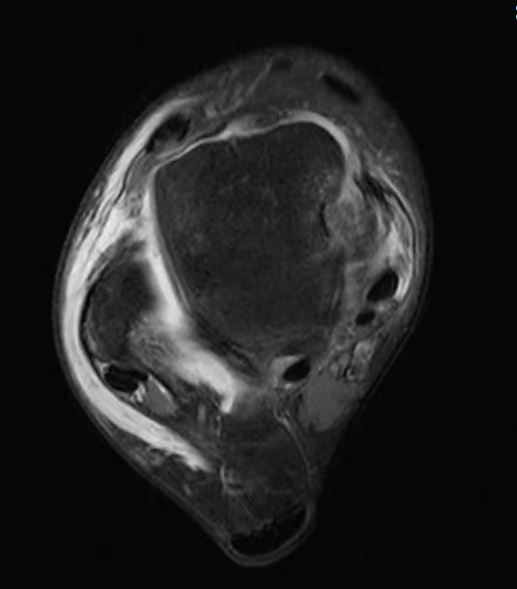

踝关节外侧扭伤后相关的综合征定义为慢性踝关节外侧不稳(chronic lateral ankle instability ,CLAD),临床查体可以很好的评估CLAD的损伤程度,MRI可以充分显示CLAD的损伤状态, 以及观察到伴或不伴踝关节软骨损伤。

11岁儿童,3天前下楼梯时扭伤后踝关节外侧肿胀明显,外踝前方压痛,MRI提示急性距腓前韧带损伤,距腓前韧带信号增高,走形冗余。